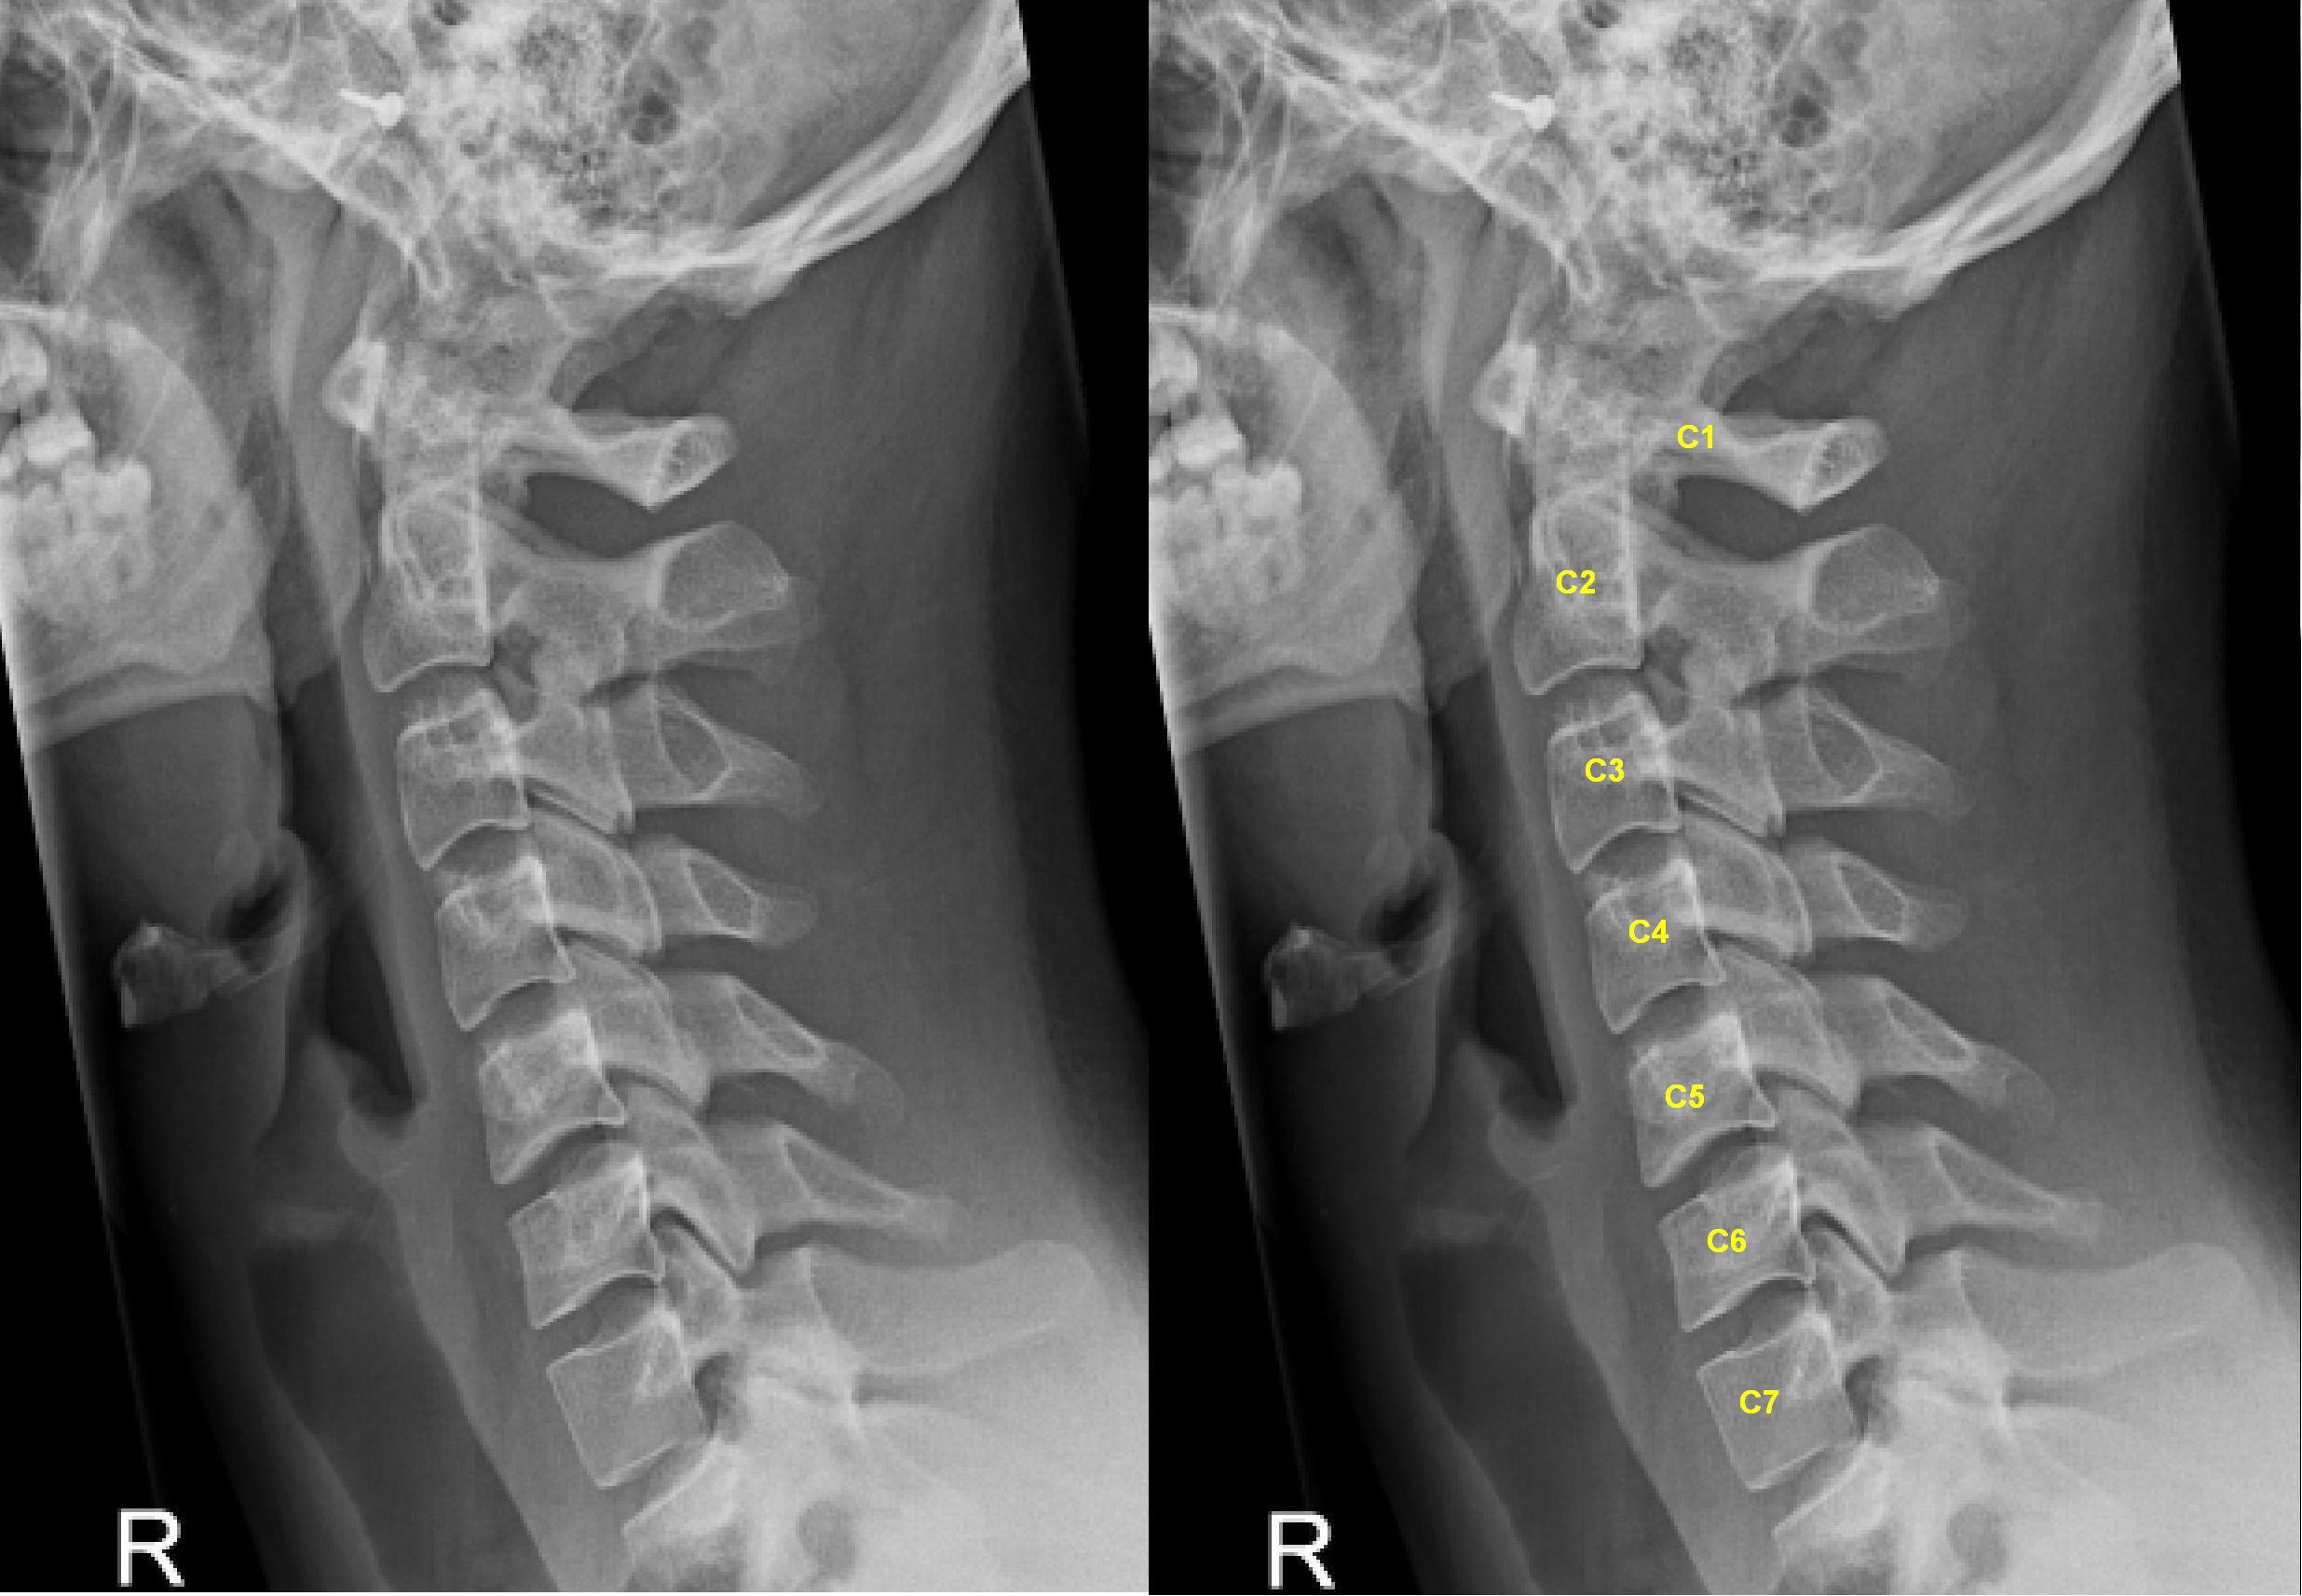

Фото:

Фото: commons.wikimedia.org, Lucien Monfils, Creative Commons Attribution-Share Alike 3.0 Unported, 2.5 Generic, 2.0 Generic and 1.0 Generic license.